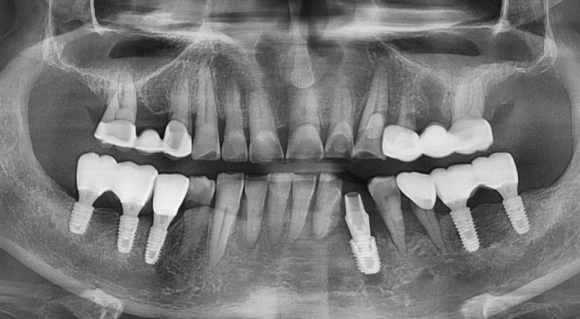

2주 후 방문 하여 결국 흔들리고 춤을추는 치아들을 발치를 하고 임플란트를 식립 하였습니다.

충분한 3D분석과 신경관과의 관계, 그리고 임플란트 모의 수술을 통한

임플란트 식립 계획을 수립하였고

총 수술 시간은 5분이었습니다.

1주 기간 치유기간을 둔 후

머리를 올려드릴 생각입니다.

보통 임플란트치유기간은 3~6개월을 기다려야 합니다.

그 이유는 임플란트와 뼈가 붙을 시간이 필요하기 때문입니다.

하지만,

환자의 빨리빨리!!! 요구, (보통 안들어드리지만 다음의 이유로 해드립니다)

하중을 많이 받는 부위가 아니라는 점

식립한 기둥이 많아서 안정적일 수 있다는 점

문제가 생길 경우 본인이 책임지겠다고 약지 걸고 약속하는점 (결국 제 책임이 되겠지만)

의 이유로 1주 뒤 머리가 올라 갈 예정입니다.

충분한 비타민과 영양섭취로 치유가 잘 되셔서

마무리를 잘 하도록 하겠습니다.